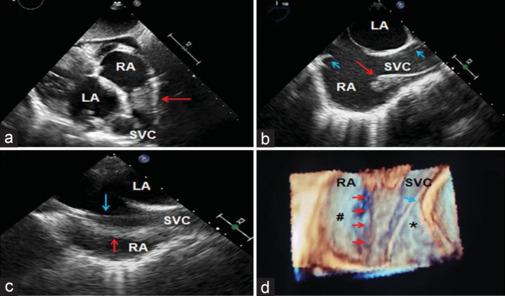

终末嵴是右心房(RA)后外侧壁上的一个新月形纤维肌脊,它将右心房光滑的后部区域与肌肉发达的前部区域分隔开来。当突出时,它经常模仿 RA 血栓、植被或肿瘤(如肌瘤)。将这种解剖结构上的变异与其他肿块区分开来对于减少误诊和避免与疾病相关的忧虑至关重要。可能需要采用不同的诊断方法,这些方法都有各自的成像特点和局限性。我们的病例强调了使用二维和三维经食道超声心动图对突出的嵴突进行鉴别的特点。

Crista terminalis is a crescent-shaped fibromuscular ridge in the posterolateral wall of the right atrium (RA) which separates the smooth posterior region of RA from a more muscular anterior region. When prominent, it frequently mimics RA thrombus, vegetation, or tumors such as myxoma. Differentiation of such anatomical structural variations from other masses is vital to minimize misdiagnosis and avoid disease-related apprehension. Different diagnostic modalities may be needed which have their own imaging characteristics as well as limitations. Our case emphasizes the differentiating features of prominent crista terminalis using two-dimensional and three-dimensional transesophageal echocardiography.